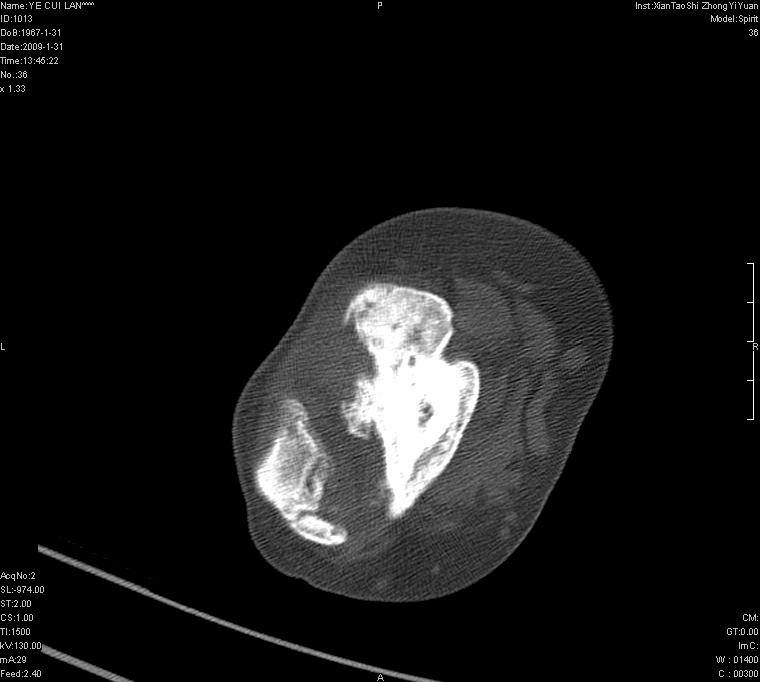

以下是引用王明发在2009-2-9 11:53:00的发言:[br]支持夏科氏关节,必要时行脊髓mri检查 [br]夏科氏关节是指由于某些神经系统疾病引起的关节病变,也被称为神经性关节炎。常见病因有脊髓痨、脊髓空洞症等。原发的神经病变可以造成关节深部感觉障碍,对于关节的震荡、磨损、挤压、劳倦不能察觉因而也不能自主地保护和避免,而神经营养障碍又可使修复能力低下,使病人在无感觉状态下造成了关节软骨的磨损和破坏,关节囊和韧带松弛无力,易形成关节脱位和连枷关节。关节面的破坏和骨赘的脱落变成关节内游离体。关节外形饱满肿胀,内有出血和渗出。这种病早期并无疼痛,不易被病人重视,仅表现为关节肿胀、无力、活动过度、动摇不稳。关节肿胀、无痛、活动范围超常是本病的重要特征。x光片可见有关节骨端广泛破坏、硬化或呈奇异形态,骨赘形成,关节间隙不规则或增宽,周围软组织钙化、关节内游离体、骨碎片等。结合x光片及临床症状,病人又有神经系统原发病症,即可确诊

以下是引用hhcckk在2009-2-9 14:31:00的发言:[br]夏科关节的六大表现[br]1.关节软组织肿胀。[br]2.关节的脱位与半脱位。[br]3.关节内的游离体。[br]4.关节面硬化,新骨形成。[br]5.骨质萎缩与破坏。[br]6.关节结构的紊乱。[br]加上患者无明显疼痛,诊断的把握性比较大